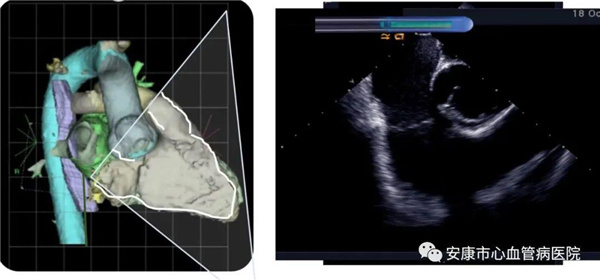

心律失常團(tuán)隊(duì)在11月6日為患者在ICE引導(dǎo)下行房撲射頻消融術(shù)。穿刺左鎖骨下靜脈,導(dǎo)絲走行證實(shí)了合并永存左上腔靜脈。穿刺右股靜脈,分別送入心腔內(nèi)超聲導(dǎo)管和消融電極,超聲下建立右心室、右心房、左心室、左心房、二尖瓣和三尖瓣及三尖瓣峽部模型。ICE就像術(shù)者多了一雙天眼,可以對(duì)心臟內(nèi)部結(jié)構(gòu)一目了然,360度無死角觀察心臟結(jié)構(gòu),可以做到“所視即所及”。建模后,消融三尖部峽部,房撲很快終止,轉(zhuǎn)為竇性心律,手術(shù)獲得成功!手術(shù)用時(shí)僅70分鐘,術(shù)后病情穩(wěn)定,安全返回病房。

心腔內(nèi)超聲(Intracardiac Echocaiography ICE)是將微型的換能器安裝在心導(dǎo)管的尖端,再經(jīng)外周血管(動(dòng)脈或靜脈)送至心腔,換能器發(fā)射聲波,然后將接受到的回波經(jīng)計(jì)算機(jī)處理后形成超聲圖像。由于換能器放置在心腔內(nèi),不受空氣等因素的干擾,因此比經(jīng)食道超聲檢查圖像更加清晰,可以辨別心內(nèi)的細(xì)微結(jié)構(gòu),臨床上主要用于指導(dǎo)心律失常的射頻消融治療。